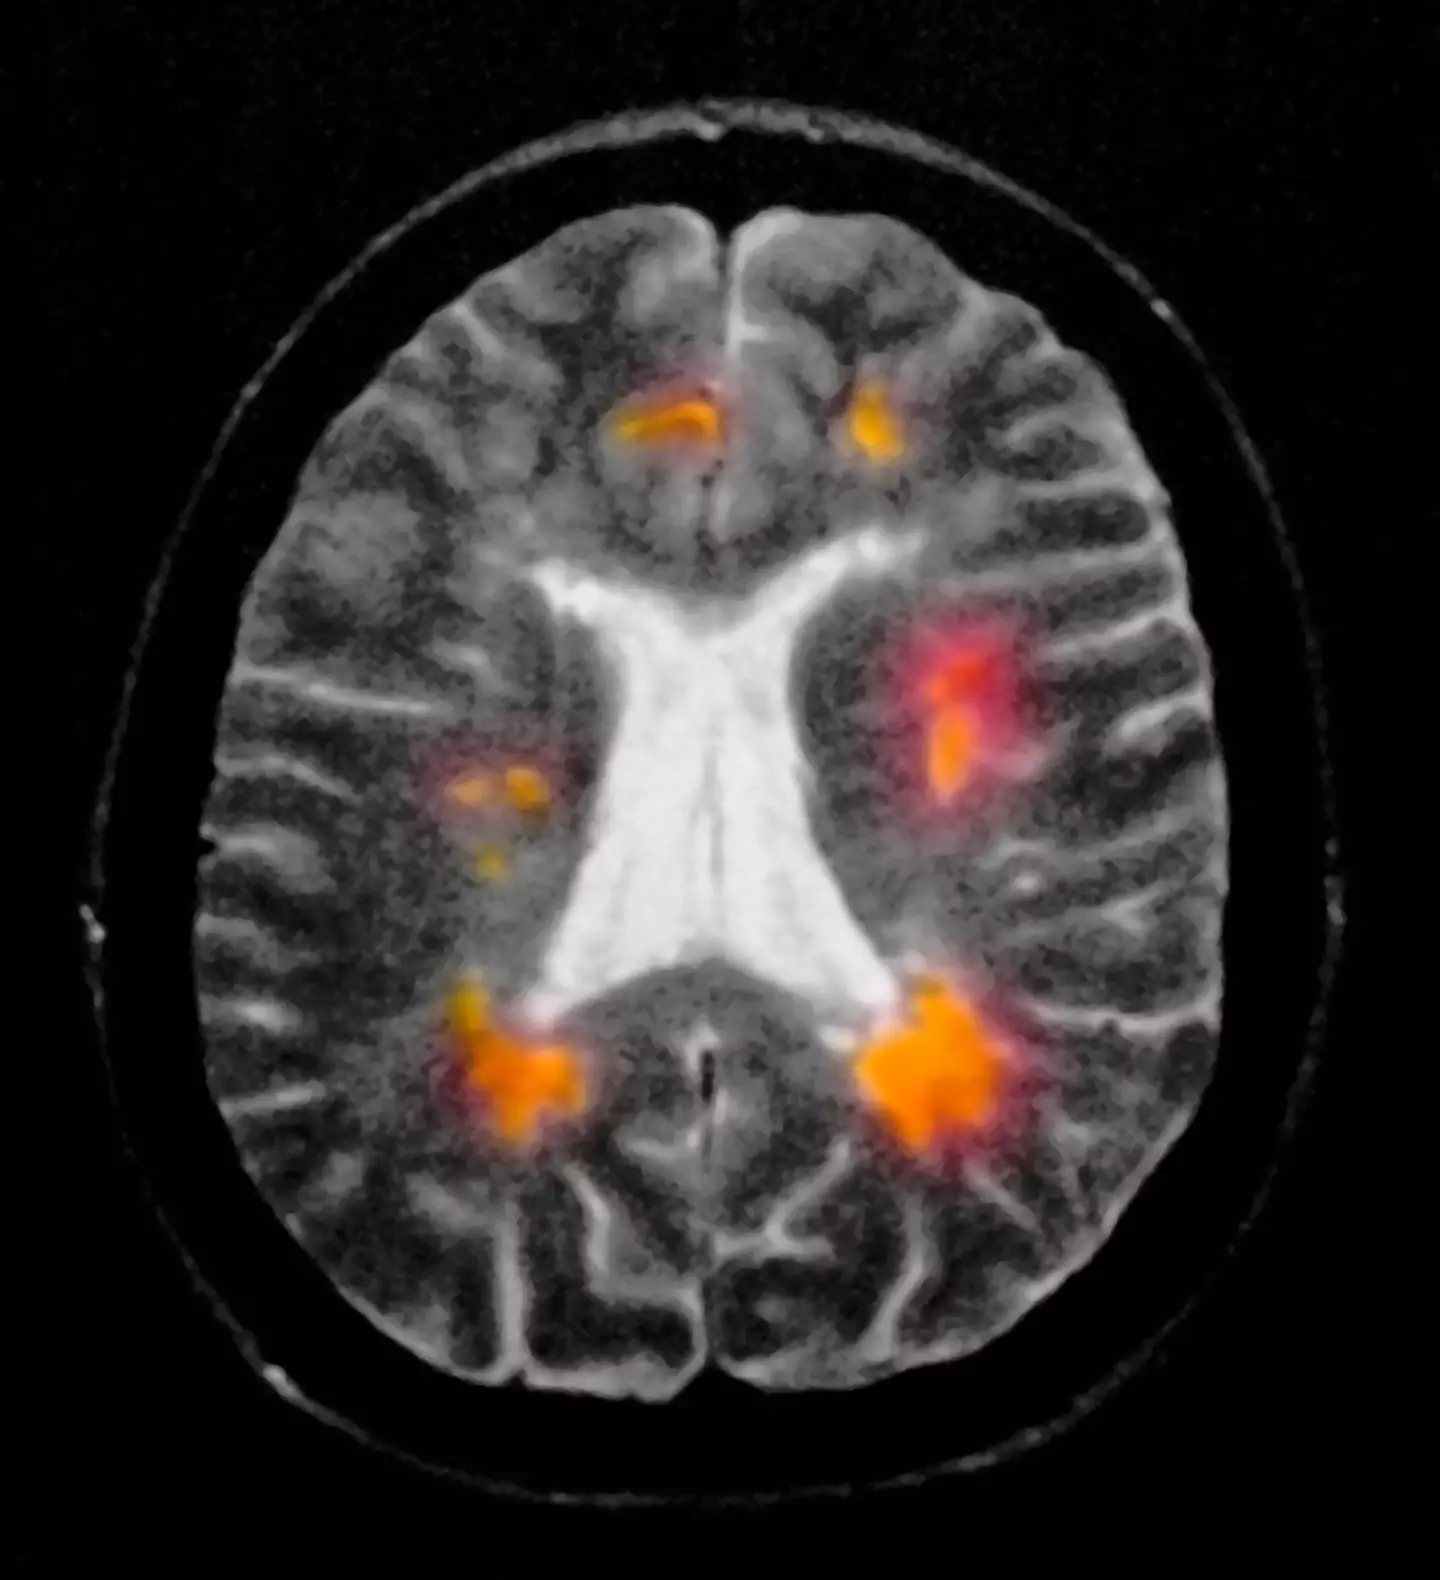

According to experts, two of the standout places include the optic nerve and the spinal cord.

Optic neuritis, inflammation around the optic nerve, is the most common.

This can present itself in the early stages as eye pain, blurred vision, and a headache.

But this only usually occurs on one side of the face, and can eventually lead to temporary or permanent loss of vision.

Optic neuritis also affects a person's perception of colour, so you may notice that colours don't look as vivid as they did prior.

Other people report that they experience flashing lights.